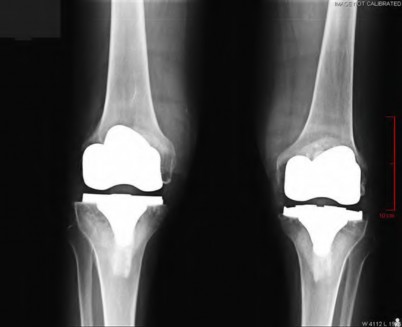

During a primary total knee arthroplasty (TKA), the surgeon evaluates the flexion and extension gaps. Utilizing spacer blocks, the surgeon notes that the extension gap is symmetric and perfectly balanced, but the flexion gap is excessively tight. Assuming an anterior referencing sizing guide was used, which of the following surgical adjustments is the most appropriate next step to balance the knee?

Correct Answer: Downsize the femoral component

Explanation:

When using an anterior referencing system, the anterior flange of all femoral components rests on the same cut surface. Downsizing the femoral component reduces its anteroposterior dimension by removing more bone from the posterior condyles. This specifically enlarges the flexion gap without altering the extension gap, thereby resolving an isolated tight flexion gap.